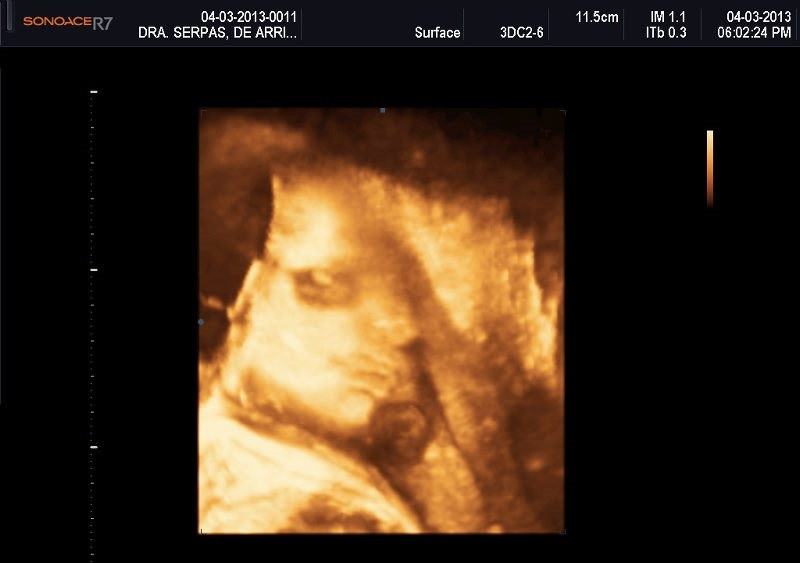

Varias ultrasonografías en 2D y 3D

Envíado por Dr. Nelson Menjívar Sarco